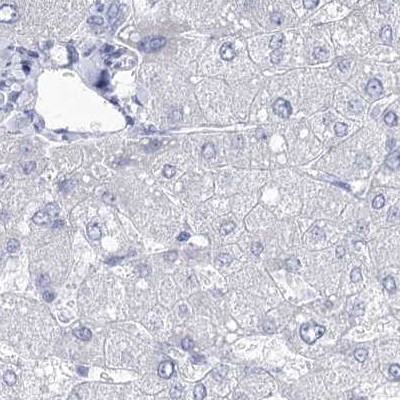

Immunohistochemistry analysis in human testis and endometrium tissues using Anti-ACRV1 antibody. Corresponding ACRV1 RNA-seq data are presented for the same tissues.